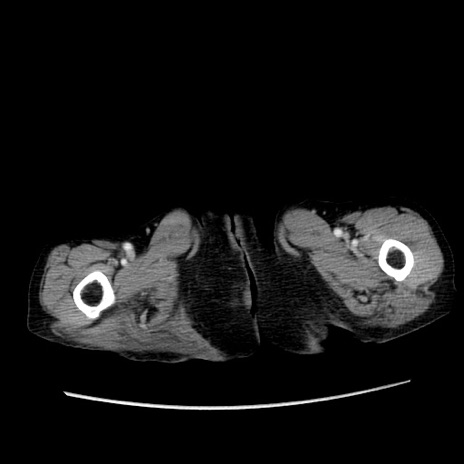

症例25(横断像)

症例

【症例】80歳代女性

【主訴】胸のつかえ感

【現病歴】約9時間前に食後から胸のつかえた感じあり、嘔吐あり、来院。

【既往歴】胃癌(全摘)、胆摘、虫垂炎

【身体所見】心窩部に圧痛あり、反跳痛なし。

【データ】WBC 5700、CRP 0.05